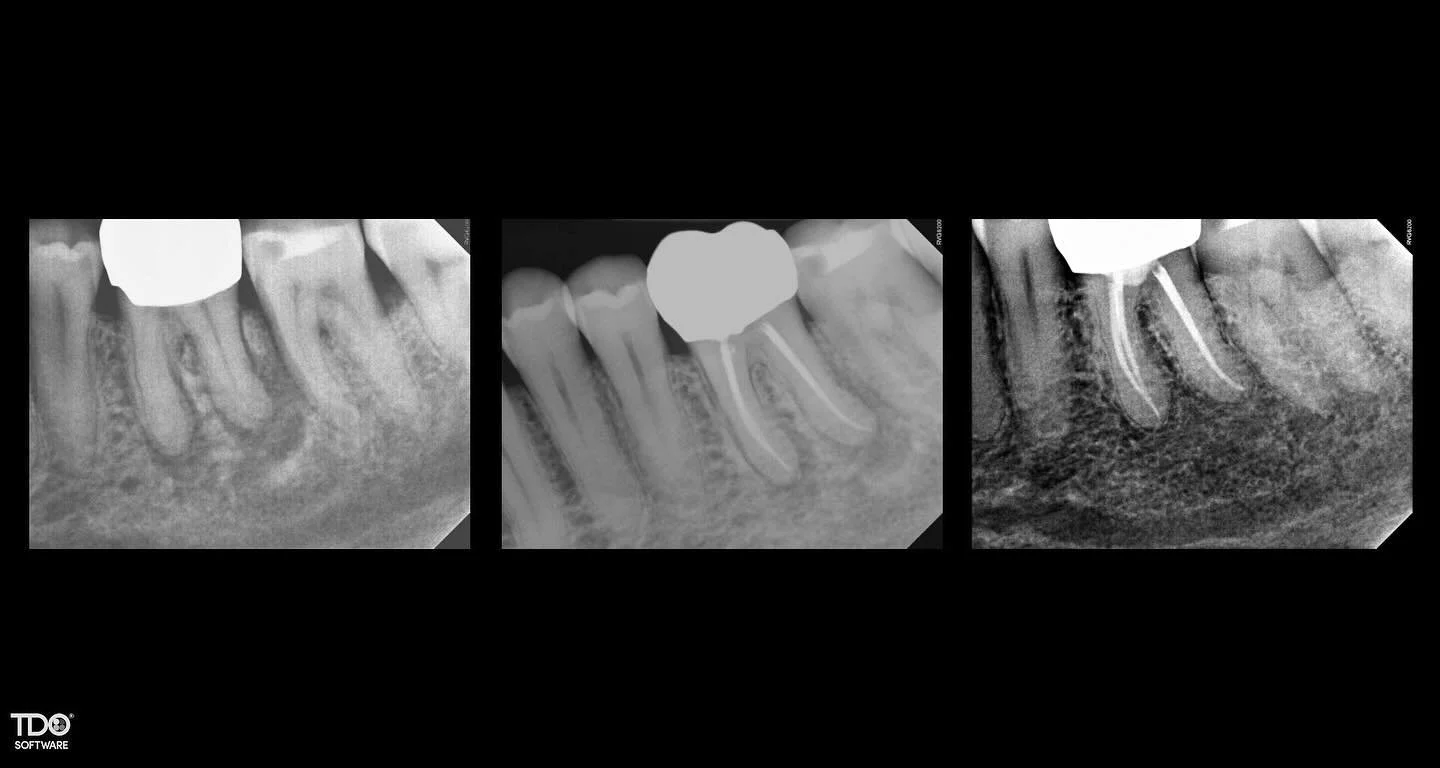

I am a board-certified endodontist with advanced specialty training and an academic interest in diagnostic reasoning, retreatment, and microsurgical endodontics. My work emphasizes CBCT-guided decision-making, interdisciplinary collaboration, and evidence-based care in complex clinical scenarios.

Board certification in endodontics represents an advanced level of professional achievement beyond specialty training. It is a voluntary, multi-year process that requires successful completion of a comprehensive written examination and rigorous peer review of complex clinical cases, evaluating diagnostic judgment, technical execution, and long-term outcomes. Less than 25% of practicing endodontists achieve board certification, reflecting a commitment to clinical excellence, continual self-assessment, and the highest standards of the specialty.